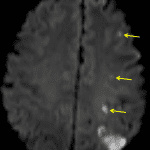

- Area of loss of gray-white differentiation in the left parietal lobe along the MCA/PCA watershed zone

- Acute left MCA/PCA and ACA/MCA watershed infarcts

Area of loss of gray-white differentiation in the left parietal lobe along the MCA/PCA watershed zone concerning for acute ischemia. No evidence of hemorrhagic transformation or associated mass effect. Recommend brain MRI without contrast for further evaluation.